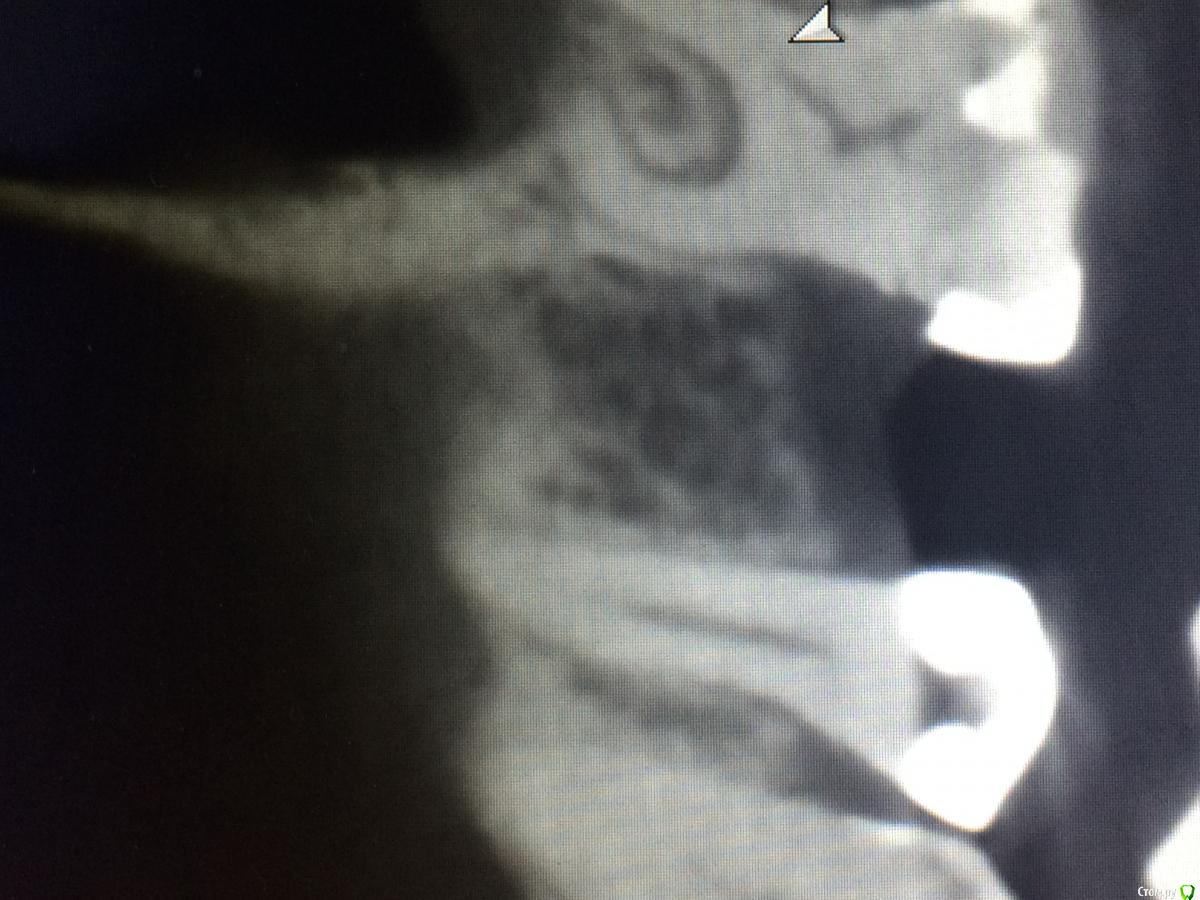

Graffwoman Опубликовано 25 февраля, 2018 Автор Поделиться Опубликовано 25 февраля, 2018 (изменено) внесу свою лепту Сосудосуживающий капли в нос на 10 дней - в каждый носовой ход Амоксиклав 1000 мг по 1 2 рд 5 дней либо супракс либо таваник - их легче принимать Бифиформ АциполНимесил 100 мг по 1 пакет 2 рд 7 дней Хлоргексидин или мирамистин - ротовые ванночки до 6 раз в день, потом сразу солкосерил дентальный наносить - он держится намного лучше других гелей и паст ,хватает трех раз в день Ну ,вообщем, это стандартный набор Из протокола хотел выяснить 1. чем сверлились ? был ли использован набор для закрытого синуса ?2. когда удаляли ( если это были Вы ) качественно ли был выполнен корежат?3.торк ?не вижу смысла трогать имплантат сейчас .Пусть заживает вторичным натяжением .Приживется - хорошо ,нет - переставите .Спасибо1.Стандартный набор Osstem2.Хороший вопрос.Прошло 1,5 года с момента удаления.Причину удаления сходу не вспомню ,но процесс был хроническим,без признаков воспаления.На верхушке корня после удаления была прикрепленная гранулема. .Кюретаж был ,как считали тогда- легкий (гранулема то вышла ),но качественный.Проба на соустье после удаления отрицательная.Сгусток формировался слабо,в лунку рыхло положила губку с йодоформом. Неожиданно лунка заживала плохо,вялотекущий альвеолит. Дополнительный неагрессивный кюретаж и промывание ХГ. .Но.... Через год- КТ и поняли,что кость не полноценная. На слизистой десны вроде легкое углубление-точка. Не придали значения,может,ревизию надо было сделать??? .Больше насторожил обьем слизистой в пазухе-до 25 мм,на сегодня -до 10). Долго ходил по ЛОРам -толку никакого. Решили оставить в надежде,может кость сформируется.,теперь снова вернулись.Всю остальную историю уже знаете. Прилагаю снимок первого КТ, по поводу размытой границы гайморовой -ничего пока не могу сказать,кажется,это просто такой ракурс. .3.Торк 45Сейчас принимает ципрофлоксацин третьи сутки по 500 мг 2р/д,антигистаминные, нимесил получается 2р/д,(тк к вечеру стал ныть снова),противогрибковые и для флоры кишечника. Как думаете ,а боль в проекции верхушки имлантата -откуда ? Изменено 25 февраля, 2018 пользователем Graffwoman Ссылка на комментарий

rytovst Опубликовано 26 февраля, 2018 Поделиться Опубликовано 26 февраля, 2018 боли одного характера ,одинаковой силы ?возможно была перфорация при удалении - трудно судить / много времени прошло вначале темы на прицельном снимке с медиальной стороны 2 витка резьбы в пазухе- может быть искажение.тут разговаривал с другим имплантологом - ставит смело при перфорациях Шнайдеровой - я не рискую.Откуда боль ? Вопрос хороший . как с перкуссией соседних зубов ? Ссылка на комментарий